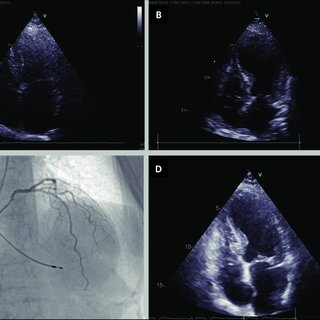

An echocardiogram, often referred to as an “echo,” uses ultrasound technology to create images of your heart. These real-time images help cardiologists evaluate how your heart and its surrounding structures are working. From observing your heart’s chambers to monitoring blood flow and valve movement, this test delivers key insights into cardiac performance.

The process of getting an echocardiogram is straightforward. The test is typically performed in an outpatient setting, taking 30 to 60 minutes. A technician will apply gel to the chest area and use a hand-held device called a transducer, which sends sound waves into your body. These sound waves reflect off your heart and create images displayed on a monitor in real time.